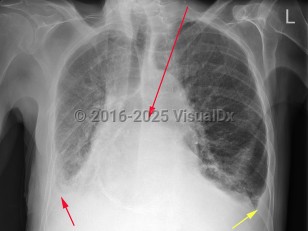

Congestive heart failureCongestive heart failure